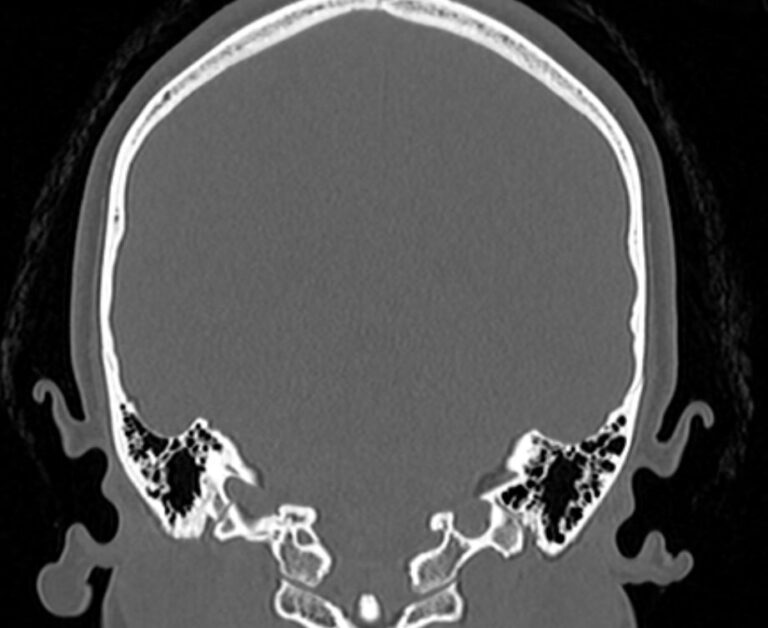

Мультиспиральная компьютерная томография является наилучшим методом диагностики патологии костей черепа. В основе методики лежит использование рентгеновского излучения с последующей цифровой обработкой полученных данных и получения трехмерных реконструкций изображений.

Костная ткань отличается высокой плотностью и способна в большой степени поглощать рентгеновские лучи. Поэтому на послойных снимках, полученных при проведении мультиспиральной КТ черепа можно детально рассмотреть свод черепа, кости лица, основание черепа. Это позволяет с наибольшей точностью визуализировать различные объемные образования, такие как остеомы, дифференцировать фиброзную дисплазию или костные метастазы. Преимуществами методики КТ является отличная визуализация костных структур, быстрота выполнения процедуры и доступная цена. Все это делает КТ незаменимой при диагностике травматических повреждений (например переломов основания черепа или орбит), аномалий развития, при планировании оперативных вмешательств.